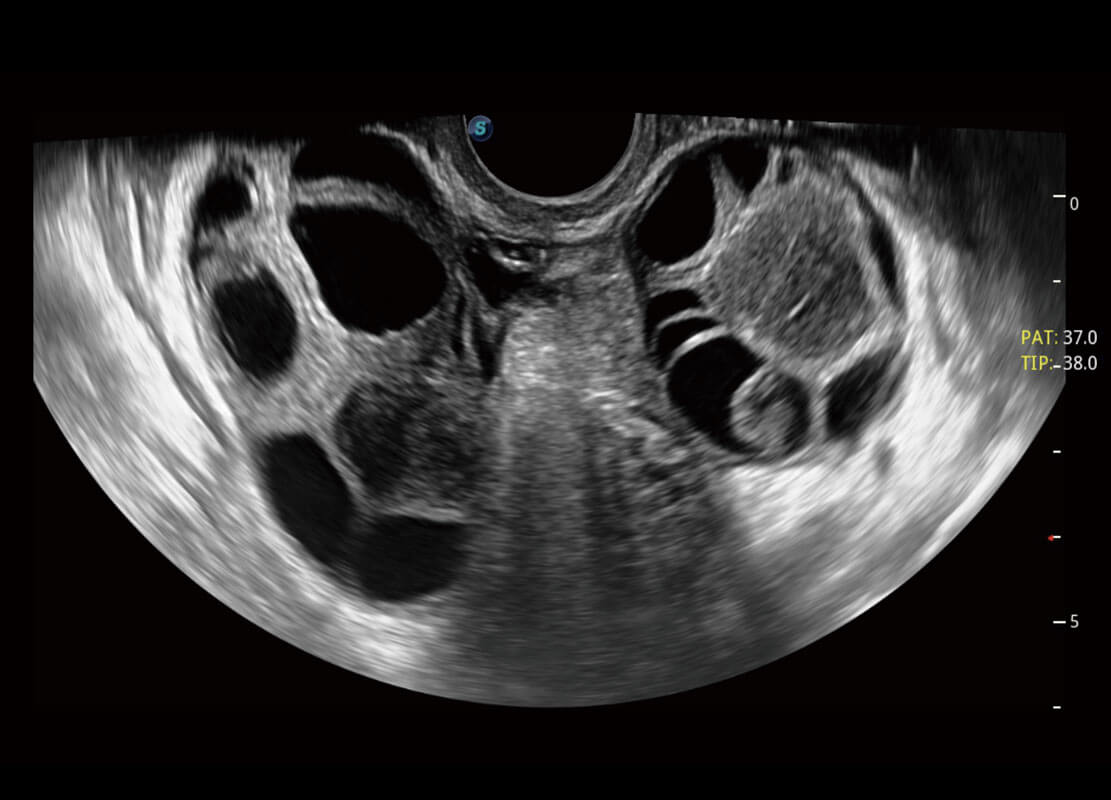

P60優(yōu)異的圖像質(zhì)量搭載??铺筋^,在婦科基礎(chǔ)疾病的診斷、卵泡生長的監(jiān)測、輸卵管通暢情況的判別等方面為您提供生殖應(yīng)用方案。

腔內(nèi)婦科-宮腔分離

腔內(nèi)婦科-卵巢